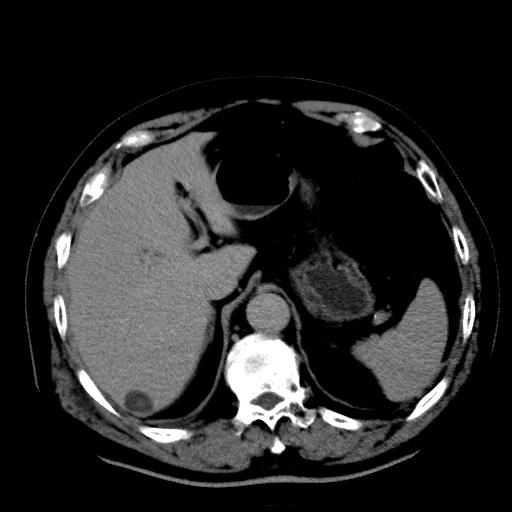

以下是引用zhctwbh在2008-8-23 14:20:00的发言:[br]囊肿合并出血

以下是引用zjb在2008-8-23 16:41:00的发言:[br]囊肿并出血可能性大。